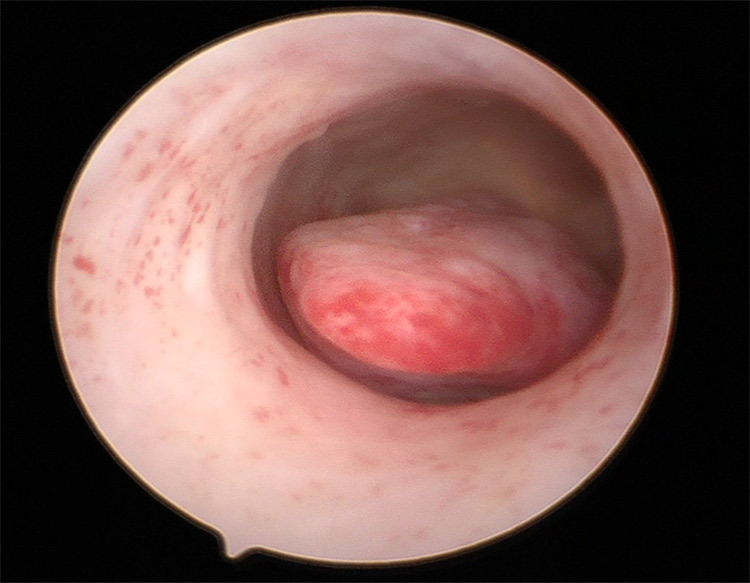

Οι παρακάτω τέσσερις εικόνες δείχνουν:

και οι δύο τελευταίες εικόνες κυστεοσκόπησης ( 3 και 4), δείχνουν πώς φαίνεται ο πολύποδας πριν την αφαίρεσή του και πώς φαίνεται το ενδομήτριο μετά την ολοκλήρωση της επέμβασης.

2. Χειρουργική αντιμετώπιση: Υστεροσκόπηση και Πολυπεκτομή

- Με μια ελάχιστα επεμβατική διαδικασία για την άμεση οπτικά εκτίμηση και αφαίρεση του πολύποδα χρησιμοποιώντας επεμβατική υστεροσκοπική τεχνική με ή χωρίς βιοψία ενδομητρίου.